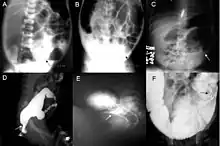

Definitive diagnosis is made by suction biopsy of the distally narrowed segment.[30] A histologic examination of the tissue would show a lack of ganglionic nerve cells. Diagnostic techniques involve anorectal manometry,[31] barium enema, and rectal biopsy. The suction rectal biopsy is considered the current international gold standard in the diagnosis of Hirschsprung's disease.[32]

Radiologic findings may also assist with diagnosis.[33] Cineanography (fluoroscopy of contrast medium passing anorectal region) assists in determining the level of the affected intestines.[34]